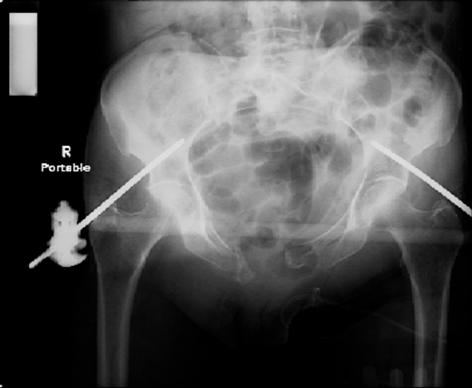

attached are images of a 70 year old female after peds versus car. her own car ran her over.

injuries are limited to the pelvis. left rami open and visible in a 10cm vertical laceration just lateral to left labia majora. wound is grossly clean. no vaginal and no urinary issues. CT scan shows widening of both SI joints anteriorly but I think this is vertically stable pattern.

pt treated that night with I/D and supra-acetabular frame to close the ring. consideration was given for SI screws bilateraly, but given time of night and other factors decision made not to proceed.

so the question is what next operatively if anything? concerns are infection, nonunion anteriorly and possible incompetence of the pelvic floor which may lead to prolapse

issues. right rami are comminuted and plating may entail ilioinguinal approach to extend plate laterally to right iliac wing. retrograde screw up right rami is an option but I am not convinced it will add much. adding SI screws very doable, but major concern is restoring anterior ring. so far wound is clean and closed over a drain, and I have no plans to open it back up and wash again.

maintaining pelvic alignment in ex-fix in 70 yo female for any length of time may be challenging.

any thoughts? would anyone plate the pubic symphysis to close the gap and leave the more lateral rami fractures alone? the most recent pelvic case on this website involved pts with suprapubic catheters and antibiotic options including resorbable beads. I wonder how many people would plate and place antibiotic beads. thanks.